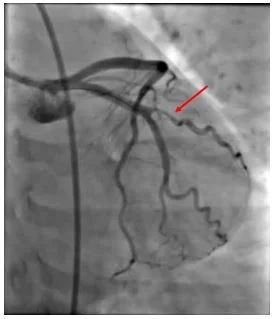

Cardiac cath: Focal occlusion of OM1, likely from a coronary dissection